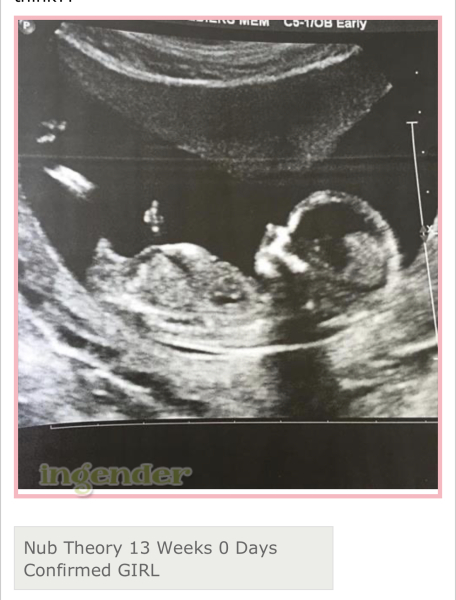

noaddedsugarx · 19/10/2023 18:26

@Goalhappy btw just to give you a bit of hope I’ve been researching and I’ve found 40+ images online where the nub looked really boyish and it turned out girl. it probs won’t happen for me but it does happen!

Here’s some

Has anyone had nub theory be wrong?